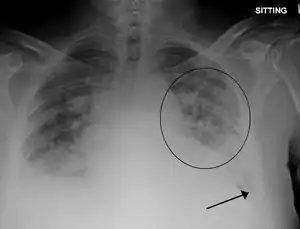

Edema pulmonar

Edema pulmonar (do grego οἴδημα, transbordar) é o acúmulo de fluido nos pulmões diminuindo a eficiência das trocas gasosas (O2 e CO2) podendo resultar em insuficiência respiratória. É uma das emergências médicas mais frequentes e pode ser fatal em poucas horas. É uma consequência comum de problemas cardíacos, vasculares ou por distúrbios da pressão pulmonar.